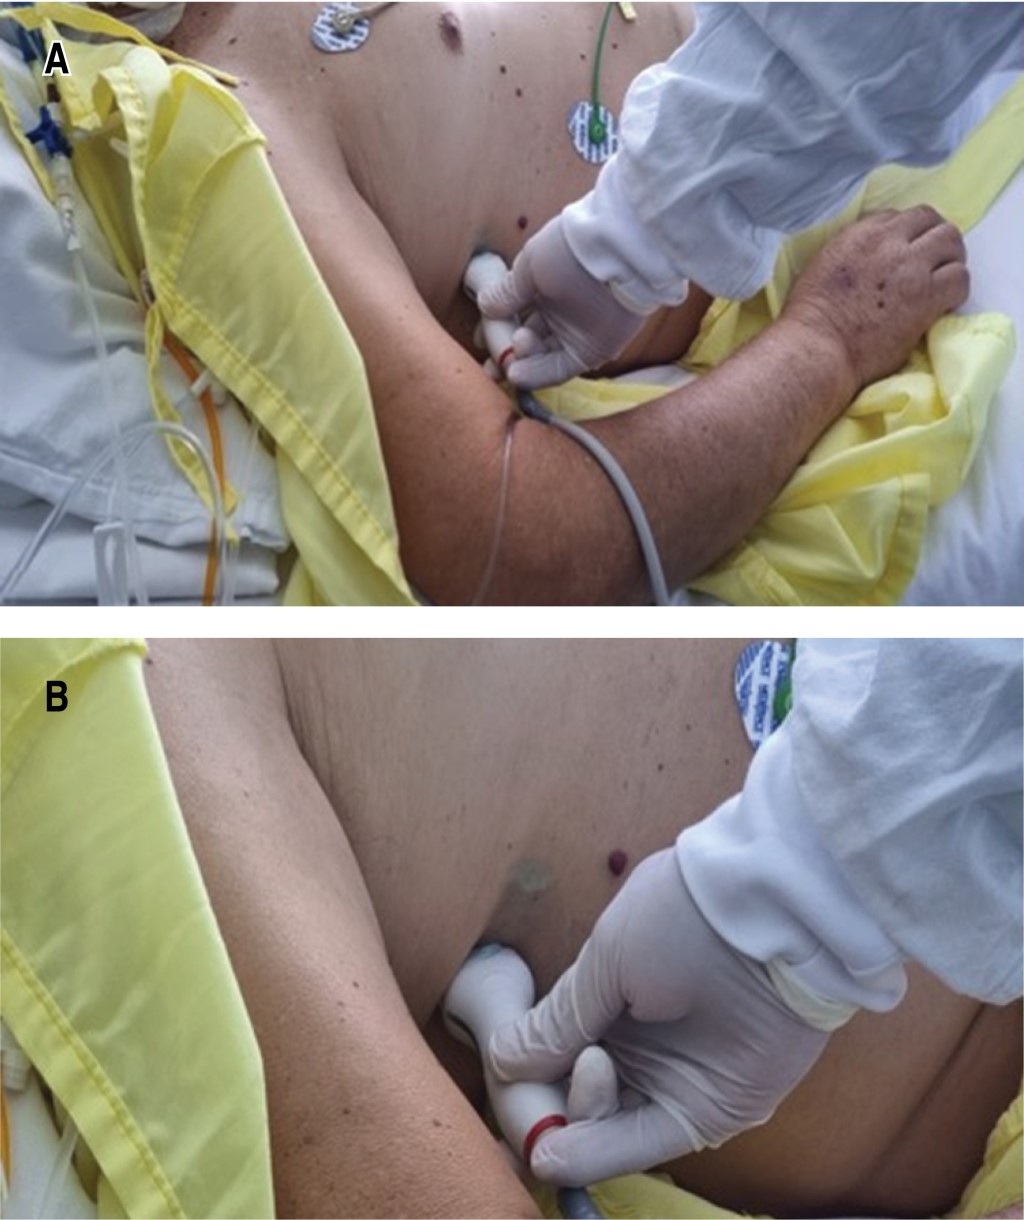

Utilidad de la fórmula de Balik para la cuantificación del derrame pleural por ultrasonido en el posoperatorio de cirugía cardiaca

Cruz-Rodríguez, Camelia1; García-Cruz, Edgar1; Gopar-Nieto, Rodrigo1; Lazcano-Díaz, Emmanuel1; Ordaz-Figueroa, Diana Lizbeth1; Elizalde-Silva, José Luis1; Rojas-Velasco, Gustavo1; Manzur-Sandoval, Daniel1